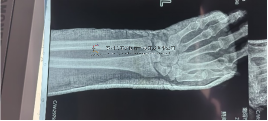

本次培訓會將于2023年6月16日-17日以“線上+線下”的形式舉辦。 本次培訓活動包括:本次會議采取線上線下結合的方式,將重點發布骨折復位機器人研發成果、3D醫學圖像處理技術實現DRF骨塊復位效果的精準評估方法、結合有限元分析分析技術助力DRF復位與固定精準化方案。

培訓將重點圍繞橈骨遠端骨折的指南研制、整復手法、臨床應用示范、優秀病例、學術經驗等層面進行深入探討與交流。